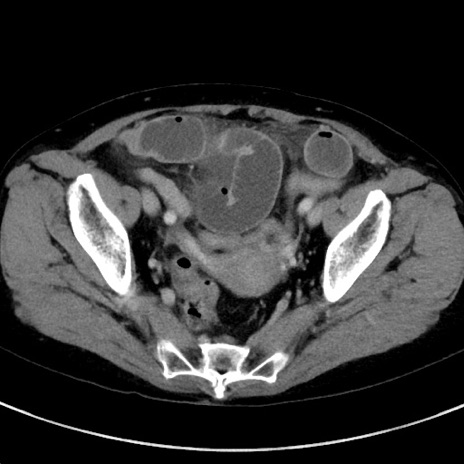

症例23(横断像)

【症例】70歳代女性

【主訴】下腹部痛・嘔吐

【現病歴】2日前より腹痛あり。昨日嘔吐あり。症状改善しないため来院。

【既往歴】胃GISTに対して胃部分切除後。

【身体所見】BT 37.1℃、BP 128/77mmHg、腹部:平坦・軟、下腹部に圧痛あり。

【データ】WBC 10200、CRP 0.31